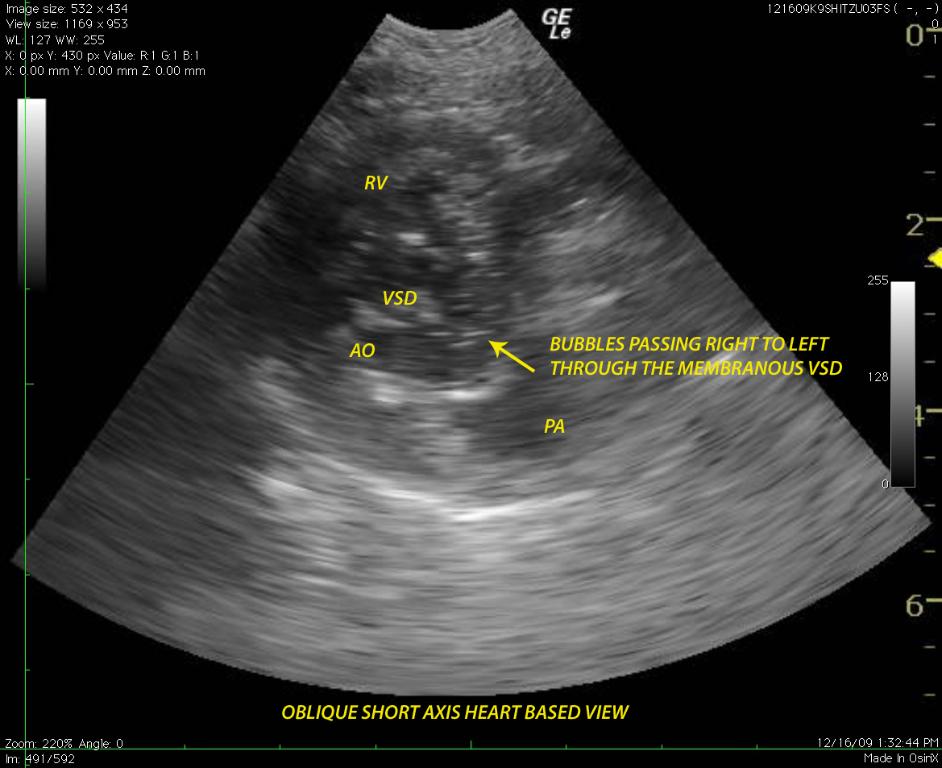

A 6-year-old FS Shih Tzu presented for exercise intolerance and cyanosis under stress. The clinical exam was otherwise unremarkable. A slight right and left sided murmur was auscultated. Right sided cardiomegaly was noted on radiographs. Radiographs (Image 1): generalized right sided cardiomegaly is noted. There is no evidence of pulmonary congestion. The lung pattern is unremarkable.